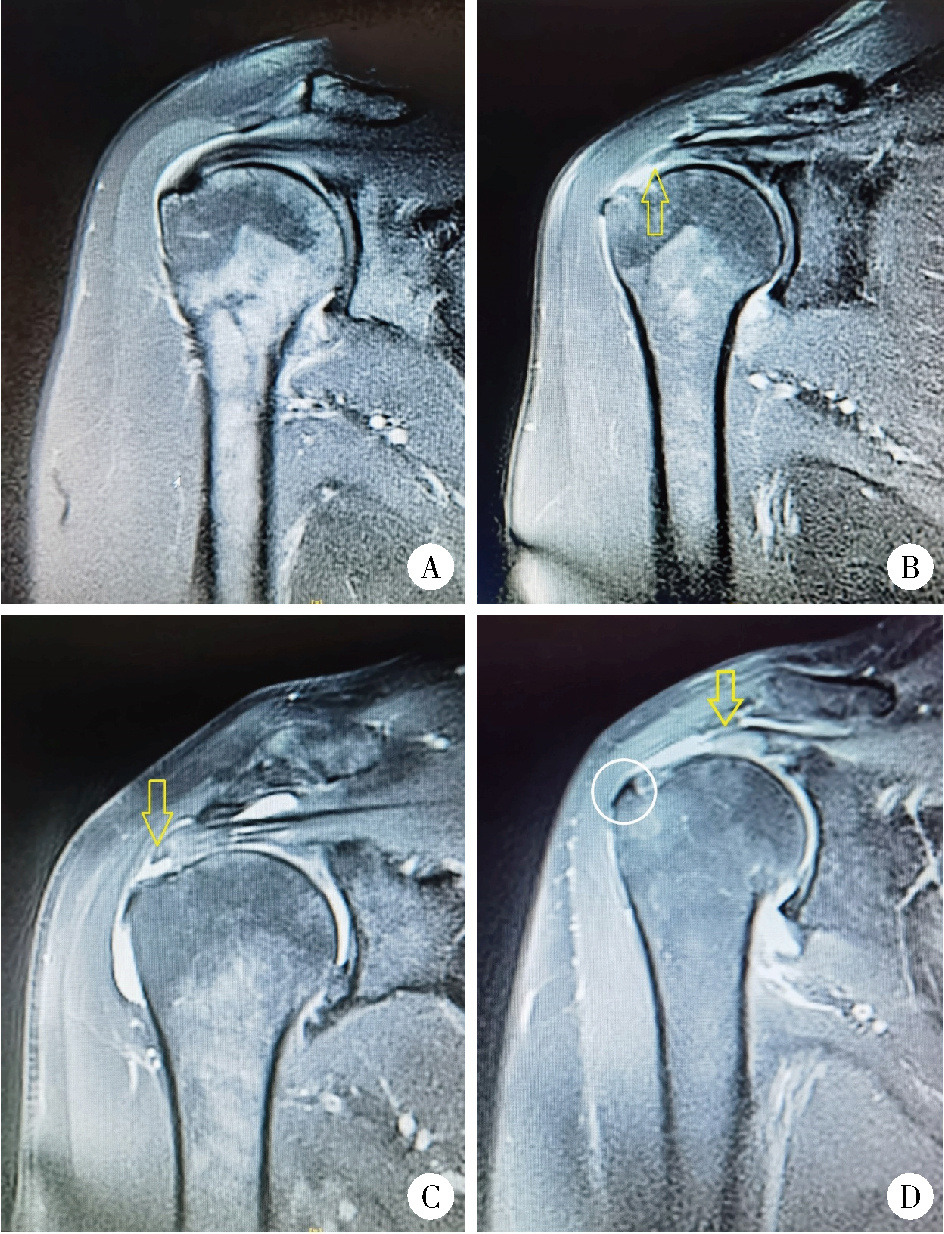

Figure 1

MRI images of patients with rotator cuff tears in each group A, negative control group; B, partial RCTs (articular side) group; C, partial RCTs (bursal side) group; D, full-thickness RCTs group. The arrow indicates the site of RCTs, the circle marks the osteophytes of greater tuberosity of humerus. RCTs, rotator cuff tears."